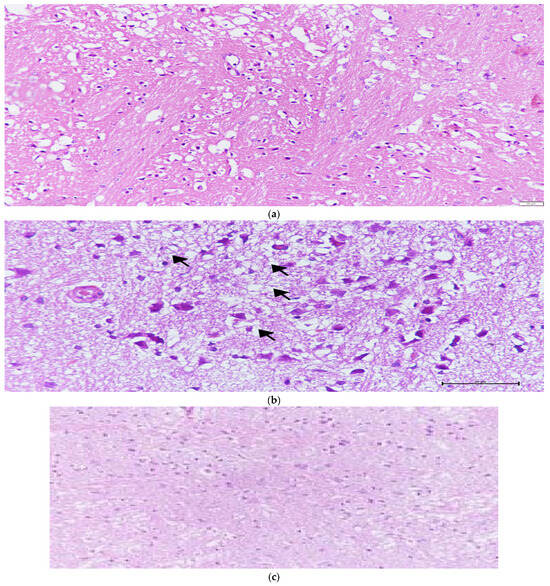

| Cellular Eosinophilic, Pyknotic Degeneration (Mean ± SD) | Vascular Congestion (Mean ± SD) | Vacuolization (Mean ± SD) | Necrosis (Infarct) (Mean ± SD) | Edema (Mean ± SD) | |

|---|---|---|---|---|---|

| Control (n = 8) | 0.75 ± 0.46 | 1.25 ± 0.46 | 0.50 ± 0.54 | 0.00 ± 0.00 | 0.75 ± 0.46 |

| I/R (n = 8) | 2.63 ± 0.52 | 1.88 ± 0.64 | 2.25 ± 0.71 | 2.38 ± 0.74 | 2.13 ± 0.84 |

| Melatonin (n = 8) | 1.63 ± 0.74 | 1.88 ± 0.64 | 1.25 ± 0.71 | 1.38 ± 1.06 | 1.25 ± 0.46 |

| NAC (n = 8) | 2.63 ± 0.502 | 1.88 ± 0.84 | 2.13 ± 0.99 | 2.38 ± 0.92 | 1.88 ± 0.64 |

| Melatonin +NAC (n = 9) | 1.67 ± 0.50 | 1.22 ± 0.44 | 1.33 ± 0.50 | 1.33 ± 0.71 | 1.11 ± 0.33 |